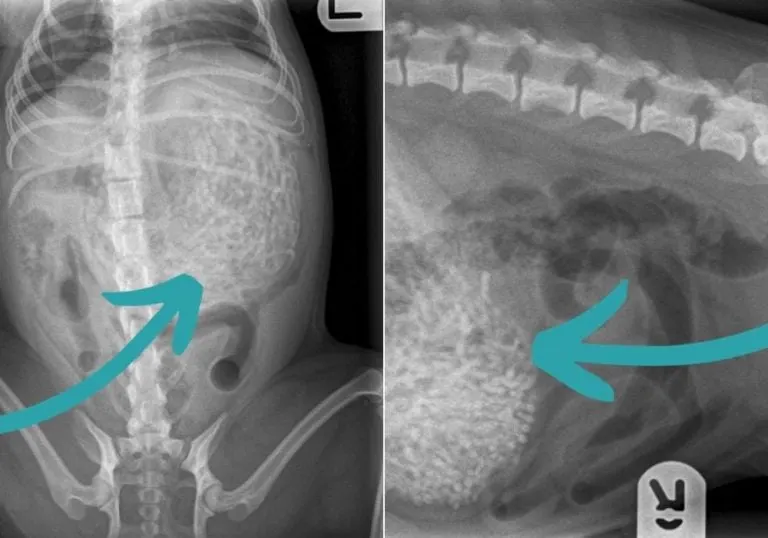

Upon arriving at the Newtone Clarke Veterinary Surgery, Ham was quickly X-rayed. The vet noticed something unusual in her stomach, but couldn’t immediately identify what it was. After a second look, he had a hunch but chose not to alarm Victoria without certainty.

It was decided that Ham needed surgery, and the vet handed her over to Emily Whitby, a skilled veterinary surgeon. After the surgery, Emily delivered news that left everyone stunned. According to the BBC, Emily revealed that they had removed “around 50 to 60 hairbands” from Ham’s stomach.

The shock didn’t end there—those hairbands weighed almost 7 ounces. Considering Ham herself weighs only about 2 pounds, it was a miracle she could function with all that inside her tiny body.